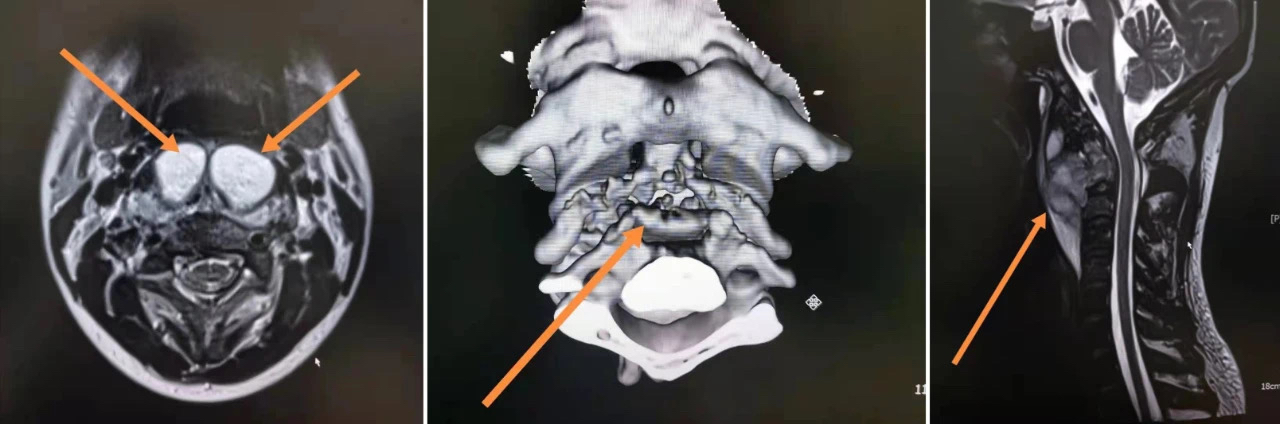

检查发现小伙骨质破坏严重,但病因是肿瘤?还是感染?或是特殊感染——结核?骨科三病区刘兴国主任医师依据影像检查提示和多年的临床经验, 最终做出了诊断:患者为枢椎体结核并寒性脓肿形成,寰枢关节半脱位。不仅这个病症名称听起来陌生,枢椎结核也属于罕见病,据可靠文献显示发病率仅在0.5%左右。

进一步检查发现,小伙的椎体破坏严重,已超过80%,继而导致枢椎齿状突出现病理性骨折,脊柱稳定性已丧失……一份病危通知单递到了小伙的家属手上。